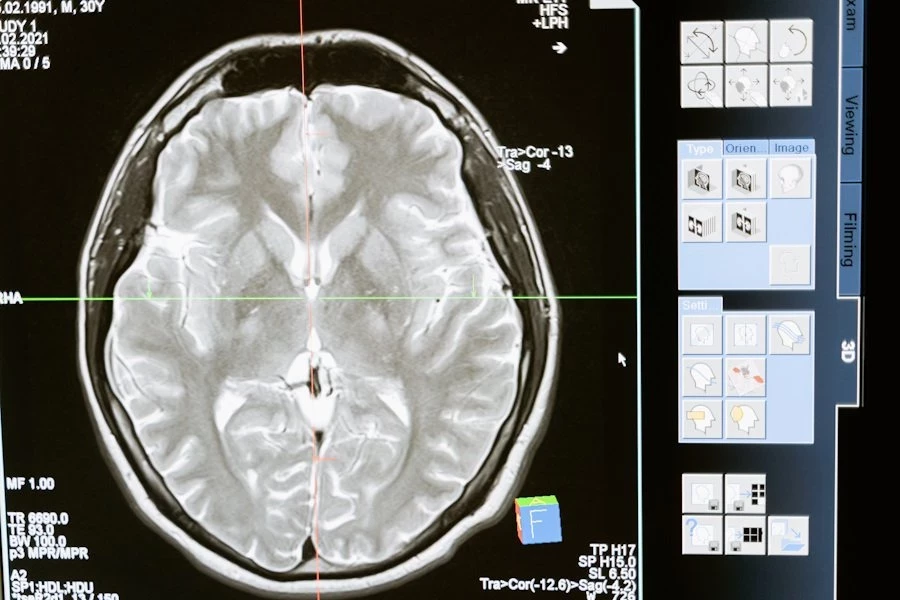

Российские учёные нашли способ остановить агрессивные опухоли мозга

Российские учёные сделали важный шаг в борьбе с одной из самых агрессивных форм рака мозга — глиобластомой. Команда исследователей нашла комбинации молекул-аптамеров, которые значительно снижают способность опухолевых клеток к делению и распространению. Это открытие может привести к созданию новых, более эффективных препаратов против глиомы, сообщает RT.

Глиобластома — это злокачественная опухоль, которая часто оказывается устойчивой к лечению. Препятствия на пути к её терапии включают сложность хирургического удаления, низкую эффективность химиотерапии из-за гематоэнцефалического барьера, а также высокий риск рецидивов.